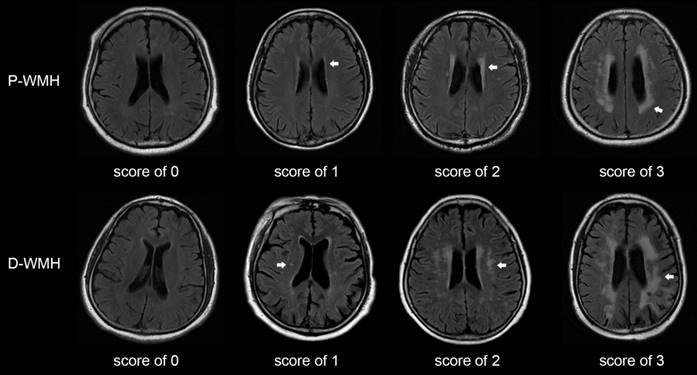

The Fazekas scale was adopted as the criterion for evaluating the severity of WMH [5]. The total WMH score was rated on an ordinal scale from 0 to 6, according to the presence, location, and range of WMH lesions on MRI. The lesions were divided into periventricular WMH (P-WMH) and deep WMH (D-WMH) according to the location, with a score of 0-3 for each location (Fig. 1). The rating criteria have been previously published [12-14]. Patients with WMH were divided into mild WMH group (total Fazekas score of 1-2) and moderate-to-severe WMH group (total Fazekas score of 3-6). Patients with P-WMH or D-WMH were respectively categorized as none/mild group (periventricular or deep Fazekas score of 0-1) and moderate-to-severe group (periventricular or deep Fazekas score of 2-3). Other CSVD signs were assessed according to the rating criteria described by Wang et al. [10].

Figure 1

Score of periventricular and deep WMH using the Fazekas scale. Periventricular WMH is graded as follows (arrow): 0=absence, 1=caps or pencil-thin lining, 2=smooth halo, and 3=irregular periventricular WMH extending into the deep white matter. Deep WMH is graded as follows (arrow): 0=absence, 1=punctuate foci, 2=beginning confluence of foci, and 3=large confluent areas. P-WMH, periventricular WMH; D-WMH, deep WMH.